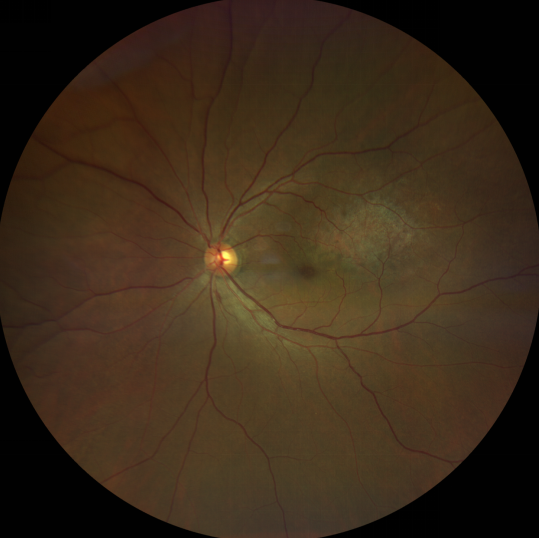

脈絡(luò)膜黑色素瘤患者在發(fā)病早期無眼痛等癥狀,當(dāng)腫瘤較小時(shí)較難發(fā)現(xiàn),隨著病程進(jìn)展,腫瘤增大,發(fā)生滲出性視網(wǎng)膜脫離或累及黃斑,視力下降才就診。

脈絡(luò)膜黑色素瘤惡性程度高,50%的患者會(huì)發(fā)生轉(zhuǎn)移,轉(zhuǎn)移到肝、肺等遠(yuǎn)處臟器,常見的轉(zhuǎn)移方式是經(jīng)鞏膜導(dǎo)管擴(kuò)散,經(jīng)視神經(jīng)蔓延者罕見。一旦發(fā)生轉(zhuǎn)移,1年生存率只有10%,即絕大多數(shù)病人在半年至1年間會(huì)失去生命。因此,早期診斷和選擇合適的治療方式對(duì)有效提高局部腫瘤的控制率、降低腫瘤的遠(yuǎn)處轉(zhuǎn)移率、延長(zhǎng)患者的生存率具有重要意義。